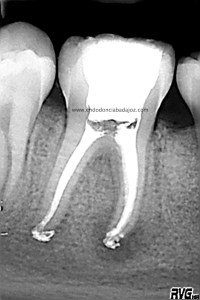

Llamamos a revisión 9 meses después a nuestro paciente:

Con estas tres proyecciones nos quedamos mucho más tranquilos y seguros de un buen sellado hermético y tridimensional des sistema de conductos de esta pieza.